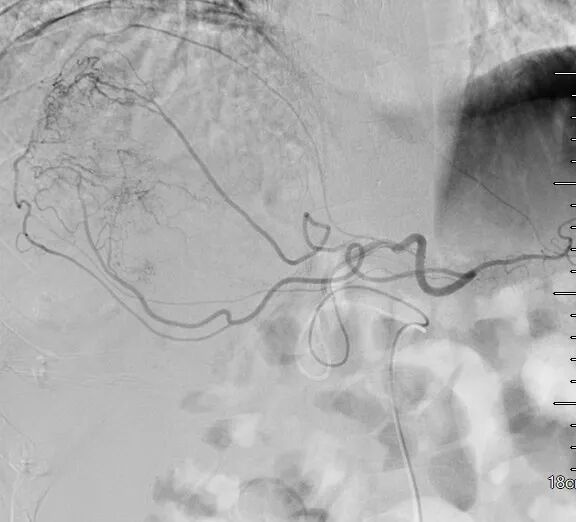

第二次D-TACE手术过程

于2020-9-24行D-TACE,术中造影发现肿瘤染色明显,较前缩小,再分别超选至肿瘤供血动脉,予表柔比星80mg+聚乙烯醇栓塞微球(蓝色型,100-300um)、2支无色型(300-500um),1支无色型(500-700um)栓塞肿瘤供血动脉,直到栓塞至肿瘤血管血流停滞。